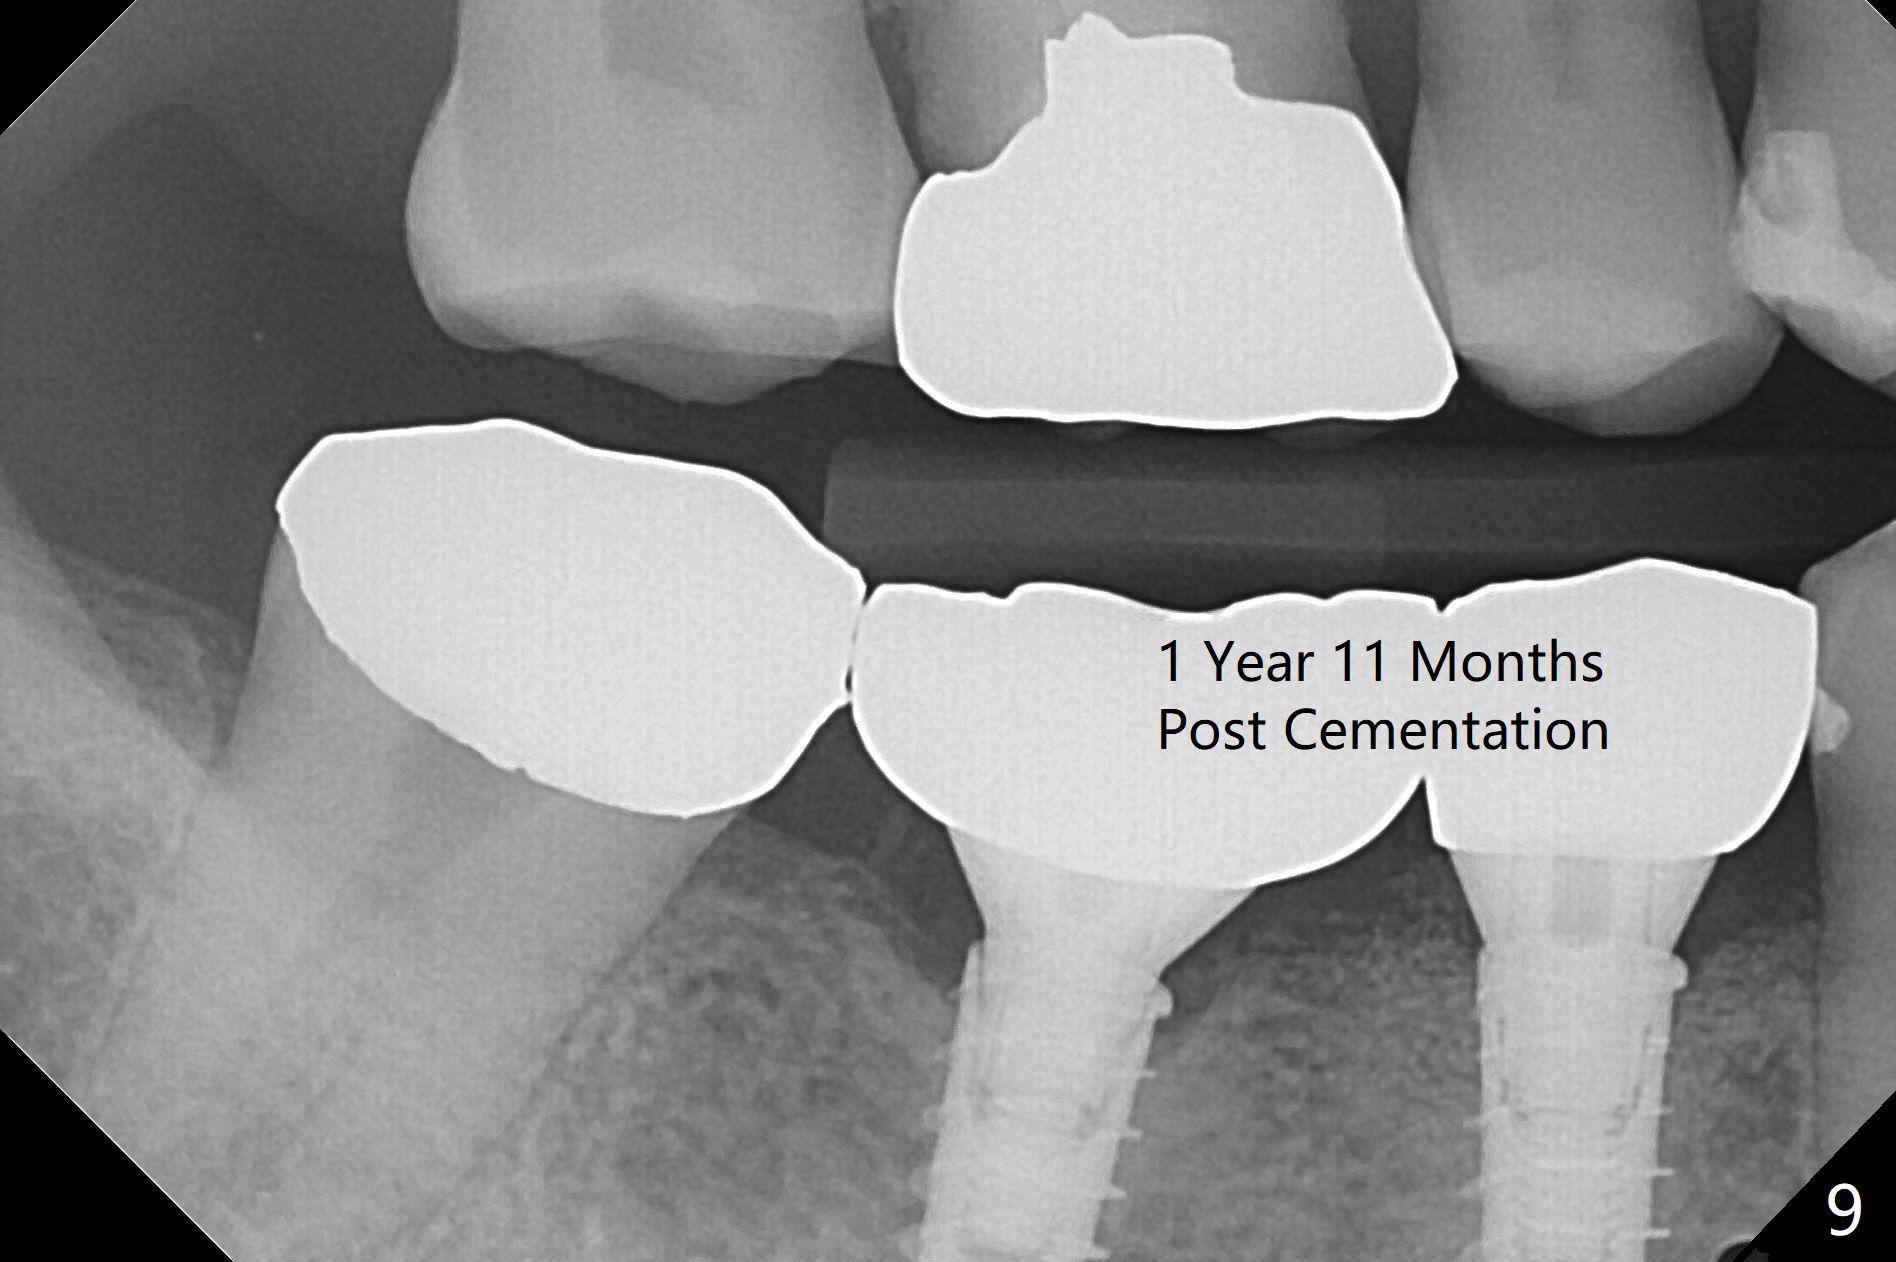

After incision, the ridge at #29 and 30 is found ~ 5 mm wide buccolingually. To place a 4x11 mm IBS implant at #30, the ridge is expanded using BEB technique (bone expansion and bending, Fig.1). It appears that the initial osteotomy at #29 is mesial (Fig.1 yellow dashed line: the distal surface of the root of the tooth #28). After moving the osteotomy distal, the final implant position at #29 (4x11 mm) is within normal limit (Fig.2). The bone at #29 seems to be not so dense that bending (using 1.6 mm drill) is not necessary (using Magic Split and Magic Expanders 3 and 3.8 mm). Later the implant at #30 (4x11 mm) is placed deeper (Fig.3). After placing bone graft around the implants/abutments and suturing, the ridge looks wider with apparent formation of the gingival bands around the abutments (Fig.4 *). Three months and a half postop, bone loss is minimal (Fig.5) and gingival bands forms around the abutments (Fig.6). Fig.7 is taken 1 month post cementation (panoramic X-ray). The patient chews normally 1 year (Fig.8) and nearly 2 years (Fig.9,10) post cementation. The crown at #31 needs recementation 2 years 7 months post #30 cementation; the incomplete seating of the abutment was noted for the first time (Fig.11). Five months later the patient is going to be retired and wants to travel abroad. After approval, the access hole was reopened; articulating paper shows under occlusion of the crown (Fig.12). Since the gap between the abutment and the implant is large, the abutment/crown complex seems to be necessary to be turned (Fig.13 curved arrow). The proximal surfaces of the crown need to be trimmed (straight lines). After turning, the crown sits down with screw tightening; the patient feels pain from the gingival cuff (Fig.14). After turning, the abutment appears to be completely seated (Fig.15). In fact the mesial and distal surfaces of the crown should have clearance from the neighboring teeth (Fig.14) so that pick-up impression is able to hold the crown/abutment complex securely (Fig.16: *). The crown is separated from the abutment after crown repair. They are seated together (loose connection) using the crown as a guide to seat the abutment. BW is taken without the crown. It appears that the abutment remains seated completely (Fig.17). The apical space is equal between #29 and 30 (Fig.17, as compared to Fig.5).